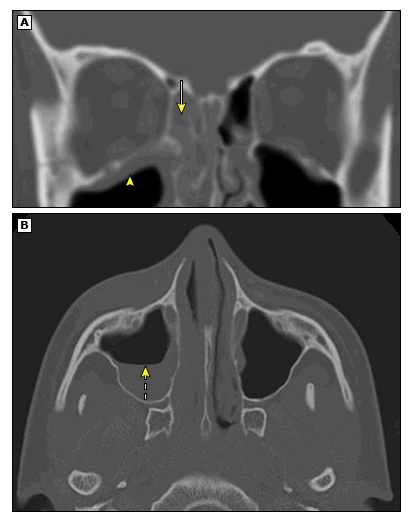

图片

图注:A:显示右侧筛窦内软组织阴影堵塞以及右侧上颌窦顶壁粘膜增厚;B:上颌窦内阴影,有液-平面,提示上颌窦积液。

• 鼻窦CT并不能很好区分急性和慢性鼻窦炎。

因为不管是急性还是慢性鼻窦炎,我们均能够从内镜上观察到鼻窦内阴影,所以一定要密切结合孩子的病史来判断。

• 影像学诊断“鼻窦炎”≠临床诊断鼻窦炎。

常有因为其他原因完善CT检查,发现鼻窦内粘膜增厚的情况,但孩子可能并无任何鼻窦炎的症状,我们并不诊断鼻窦炎。

如上图所示,齿科拍摄牙片时发现筛窦粘膜有轻微增厚(箭头所示),但孩子仅在2周前有过“感冒”表现,目前已经自愈。这种情况考虑是急性鼻窦炎恢复期,不一定需要治疗。